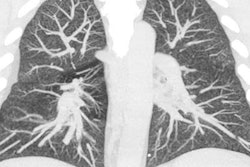

The researchers, led by Dr. Mateusz Karwowski and Benjamin Blount, PhD, of the CDC, analyzed the bronchoalveolar lavage fluid samples of 51 patients with electronic cigarette (e-cigarette), or vaping, product use-associated lung injury (EVALI). They detected vitamin E acetate in the lung fluid of 94% of the samples, as well as THC in 85% and nicotine in 64% of the cases. (The findings corroborated a previous CDC bulletin reporting the presence of vitamin E acetate in 29 vaping cases.)

In contrast, they found no trace of vitamin E acetate in any of the 99 healthy participants assessed, including 18 individuals who used e-cigarettes but did not have confirmed EVALI.